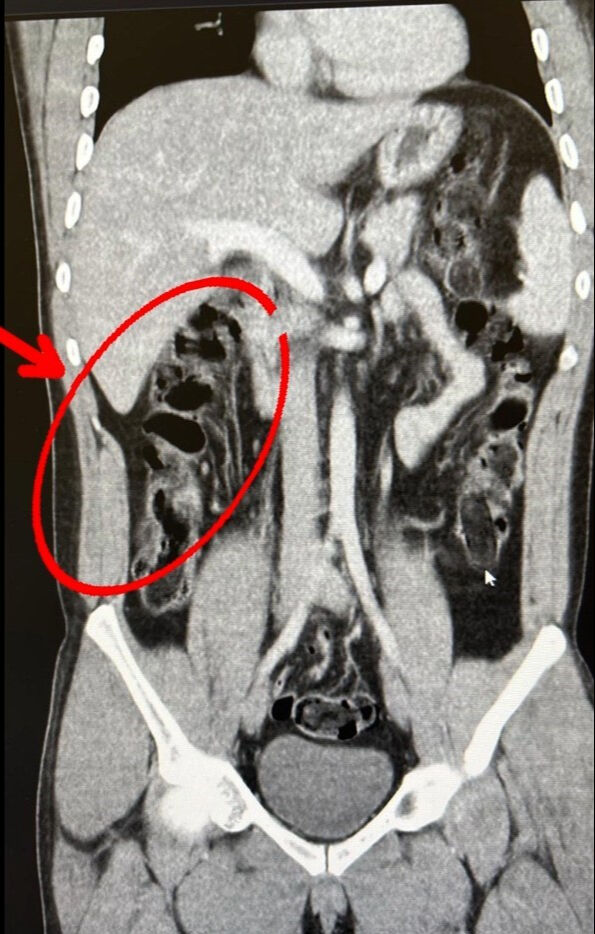

S.S. ve F.M.K. isimli şahısların hastanede yapılan iç beden muayenesi sonucunda 35 kapsül halinde toplam 278 gram eroin maddesi ele geçirildi. Şüphelilerin havalimanındaki görüntüleri, yakalandıktan sonra muayene edilme anları ve yuttukları kapsüllerin yer aldığı film sonuçları kameralara yansıdı.